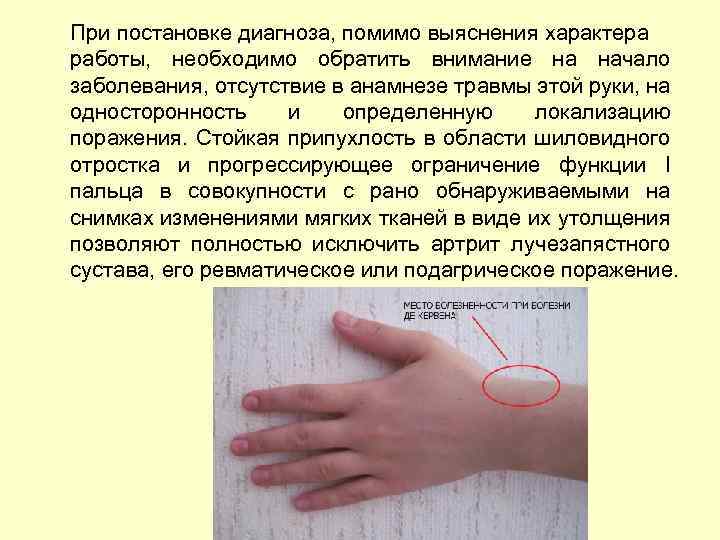

Стилоидоз Стенозирующий лигаментит тыльной связки запястья по ходу l-гo канала (болезнь де Кервена)

При постановке диагноза, помимо выяснения характера работы, необходимо обратить внимание на начало заболевания, отсутствие в анамнезе травмы этой руки, на односторонность и определенную локализацию поражения. Стойкая припухлость в области шиловидного отростка и прогрессирующее ограничение функции I пальца в совокупности с рано обнаруживаемыми на снимках изменениями мягких тканей в виде их утолщения позволяют полностью исключить артрит лучезапястного сустава, его ревматическое или подагрическое поражение.